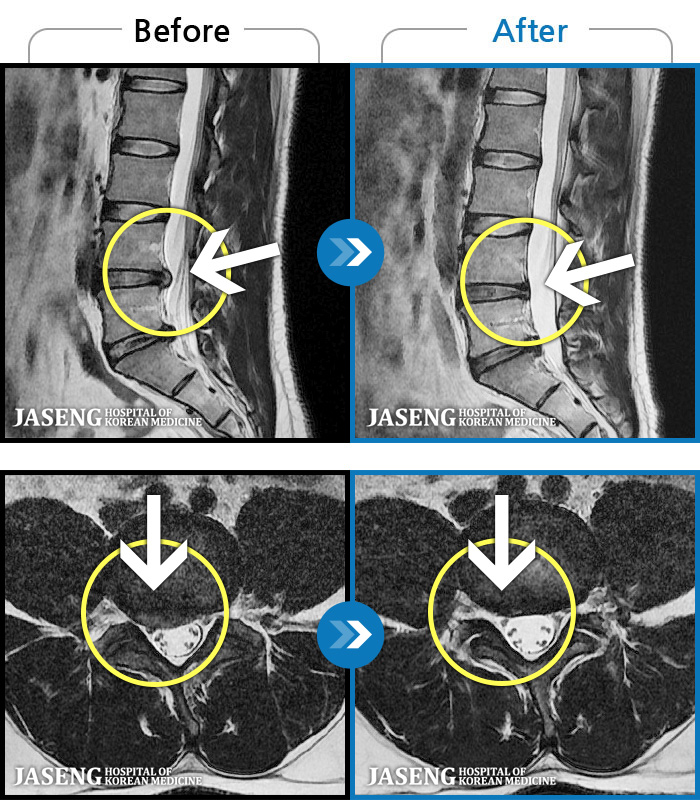

1,240 MRI ũ ʸ Ȯϼ.

ȯںп Ǹ ǿ ԿǾ, ο ġ ۿ Ƿ ġḦ Ͻñ ٶϴ.